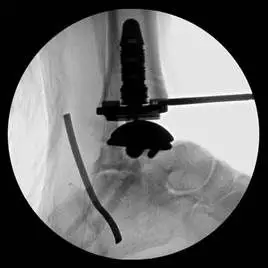

This is a pic of the implant getting mapped out for placement in the distal tibia

This is the guide for the tibia component of the implant